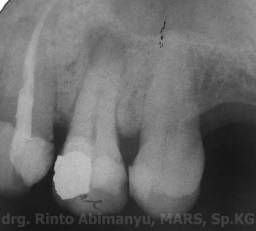

Pasien awalnya datang dengan keluhan tambalannya pecah dan sering terselip makanan. Selain itu gigi tersebut kalau dipakai menggigit agak terasa tidak nyaman… Saya lakukan pemeriksaan objektif pada gigi yang dikeluhkan, terlihat gigi 24 ada tambalan amalgam di bagian mesial, sedangkan di bagian distal sudah tidak ada tambalan.. Kavitasnya terdapat karies sekunder, perkusi positif, respon dingin negatif….

Ini kondisi gigi tersebut…

Keadaan klinis gigi 24 saat awal datang

Dari hasil pemeriksaan radiografis terlihat kavitas sudah mengenai pulpa, dan ada lesi periapeks..

Radiografis gigi 24